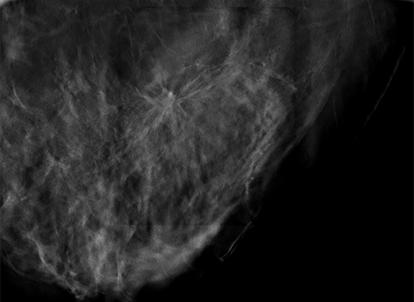

Superior imaging capability and a wider field of view.

With high quality 2D or tomosynthesis (3D™) imaging and a field of view that’s more than 6.5 times larger than older generations of prone biopsy systems,1 clinicians can visualize more tissue and pinpoint subtle lesions and faint calcifications that may not be visible on older systems. It also allows for easy software upgrade from 2D to 3D imaging at any time.